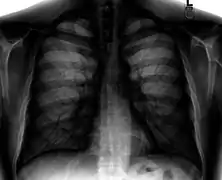

.jpg.webp)

Different views (also known as projections) of the chest can be obtained by changing the relative orientation of the body and the direction of the x-ray beam. The most common views are posteroanterior, anteroposterior, and lateral. In a posteroanterior (PA) view, the x-ray source is positioned so that the x-ray beam enters through the posterior (back) aspect of the chest and exits out of the anterior (front) aspect, where the beam is detected. To obtain this view, the patient stands facing a flat surface behind which is an x-ray detector. A radiation source is positioned behind the patient at a standard distance (most often 6 feet, 1,8m), and the x-ray beam is fired toward the patient.